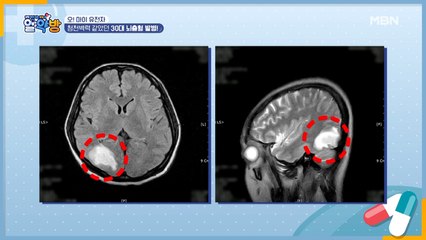

호르몬 이상 증세 & 자궁경부암으로 자궁과 난소까지 절제